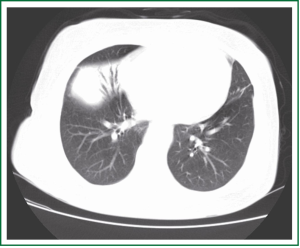

A 61-year-old female nonsmoker presented with a chief complaint of fever and cough. Chest computed tomography (CT) scan showed partial consolidation of the right middle lobe and patchy shadow in the right lower lobe. Fever and cough were not completely relieved after two weeks of anti-inflammatory treatment. A second CT revealed a lump (6 cm × 5 cm ×3 cm) in the right middle lobe (Figure 1). A subsequent right middle lobectomy was performed. In the resected lobe, we found a lump with the dimension of 5 cm × 4 cm × 3 cm. Cut section of the lump was grey and scattered with necrosis. Pleura was locally involved.